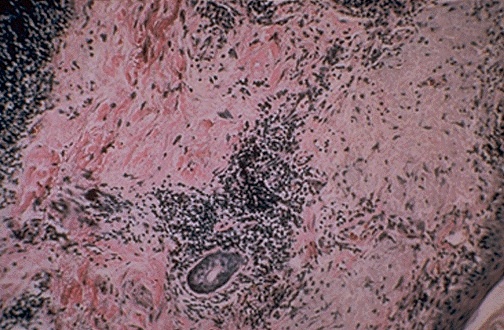

| Histologically, the skin of a patient with SLE may demonstrate a vasculitis and dermal chronic inflammatory infiltrates, as seen here. Vasculitis with autoimmune disease (often related to deposition of antigen-antibody complexes) can occur in many different organs and can lead to the often confusing signs and symptoms of patients with rheumatic diseases. [Image contributed by Elizabeth Hammond, MD, University of Utah] |